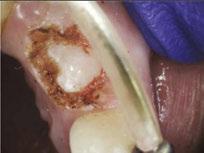

Figure 1: Preoperative periapical radiograph of tooth No. 30 with a large radiolucent lesion approximating the distal pulpal horn and a smaller radiolucent lesion closer to the mesial marginal ridge Figure 3: Conservative removal of all carious dentin on all axial walls and pulpal floor. No clinical pulpal exposure noted, but likely very close to distal buccal pulp horn Figure 2: Large active carious lesion involving the entire distal buccal cusp and surrounding aspect of tooth No. 30. Smaller Class VI lesion located on the mesial lingual cusp on No. 30 Figure 4: Placement and curing of two separate thin layers of NeoLINER over the dentin. Image depicts the NeoLINER following the indirect pulp cap of tooth No. 30